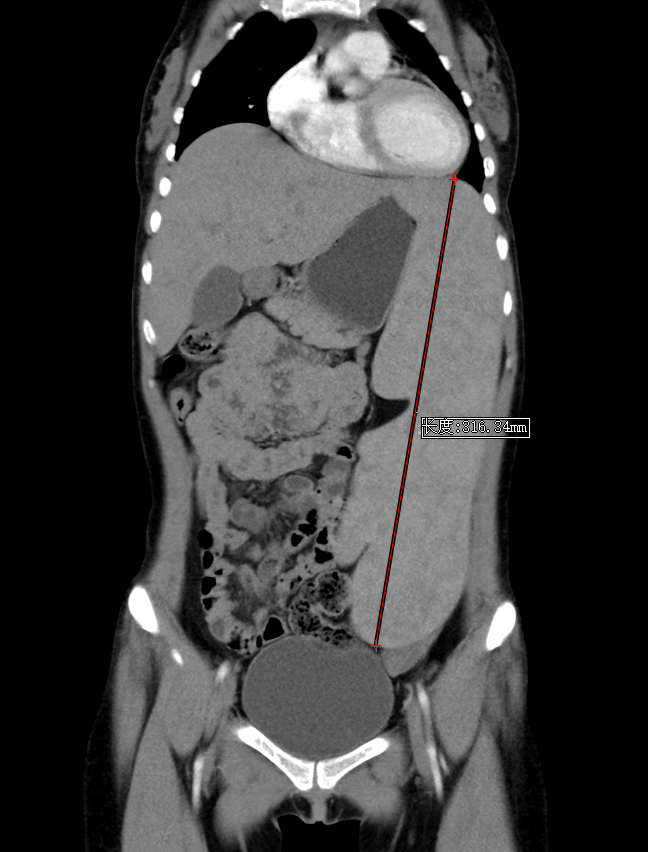

胸腹部增强CT:1.脾脏重度肿大,最大径线超过30cm,脾静脉明显增粗,考虑门脉高压。2.心室及大血管血液密度减低,考虑贫血。

CT示脾脏重度肿大,最大径线超过30cm